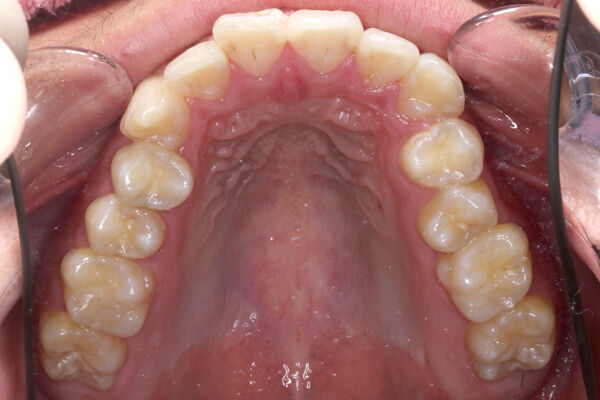

画像で見てみましょう。

画像では向かって右に見えるのが患者さんの左側です。

患者さんの右側(画像だと左側)よりもへこんでいるのがわかります。